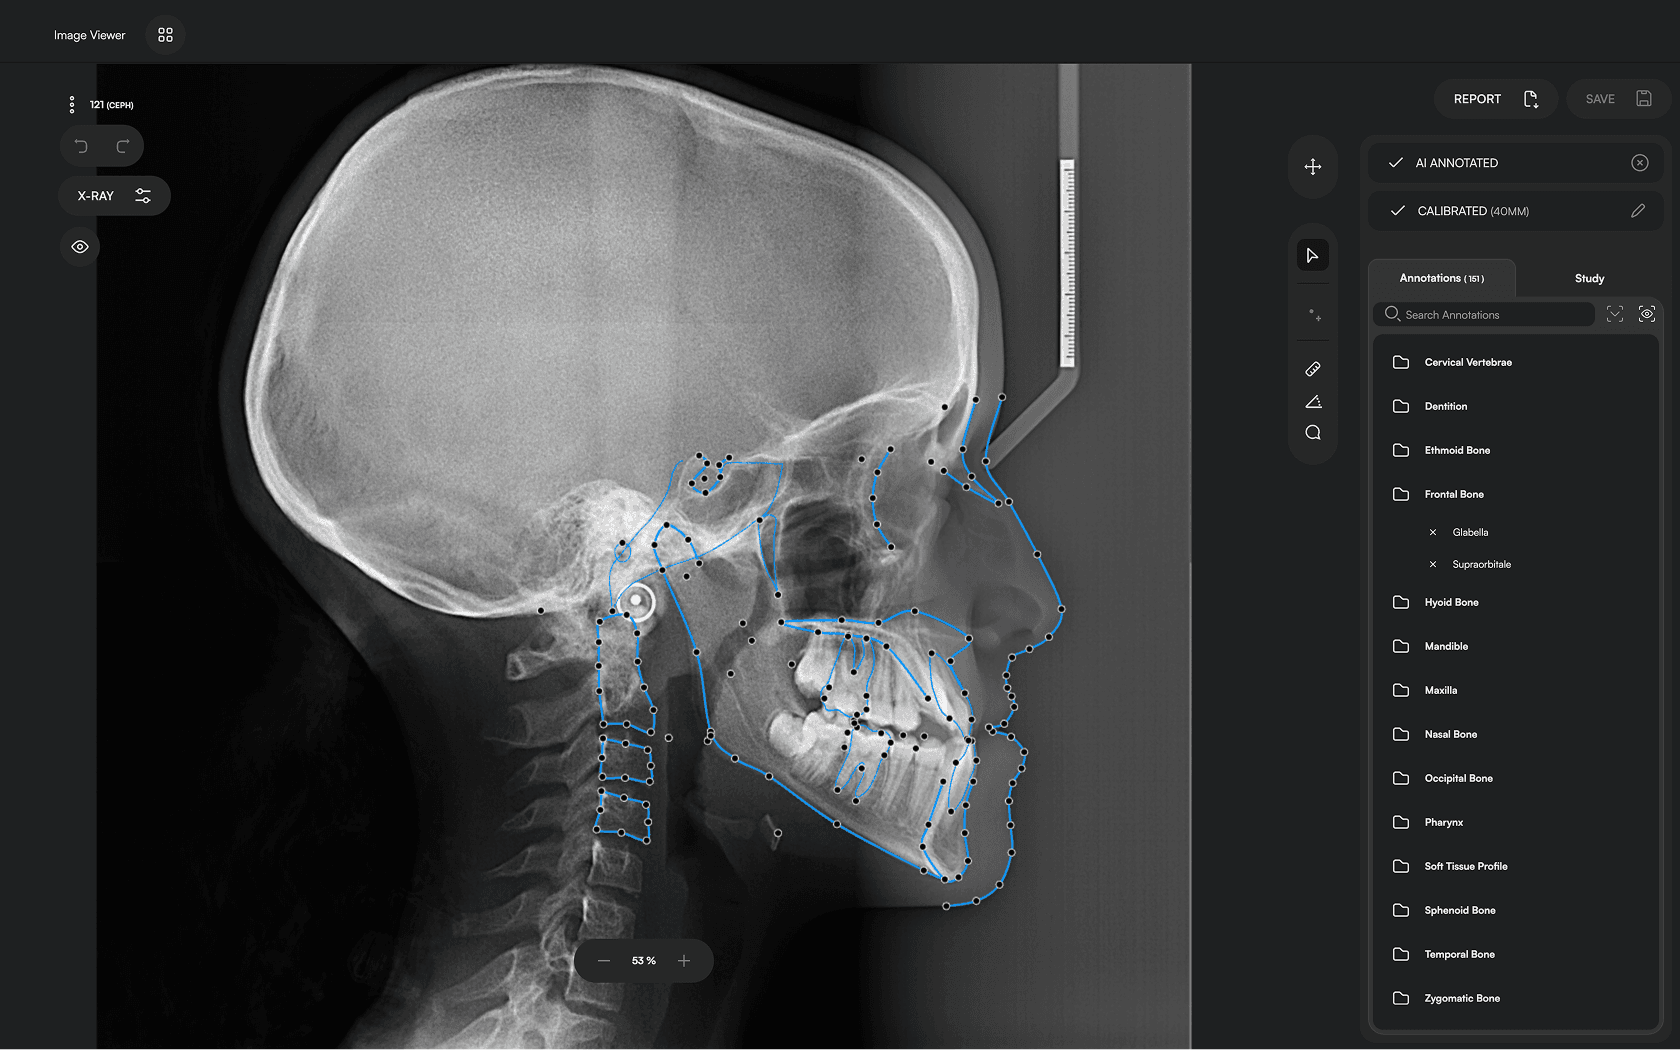

150+ landmarks traced in seconds

Identify 150+ orthodontic landmarks in under 10 seconds — a task that

traditionally may take more than 30 minutes.

Diverse Analysis

Access automated studies like Steiner and Jefferson to assist in clinical assessment and enhance case evaluations.

Experience a comprehensive assessment of skeletal, dental, and soft tissue discrepancies.

Clear Reporting

Create concise, clear reports to build confidence, enhance patient

communication and ensure transparency.